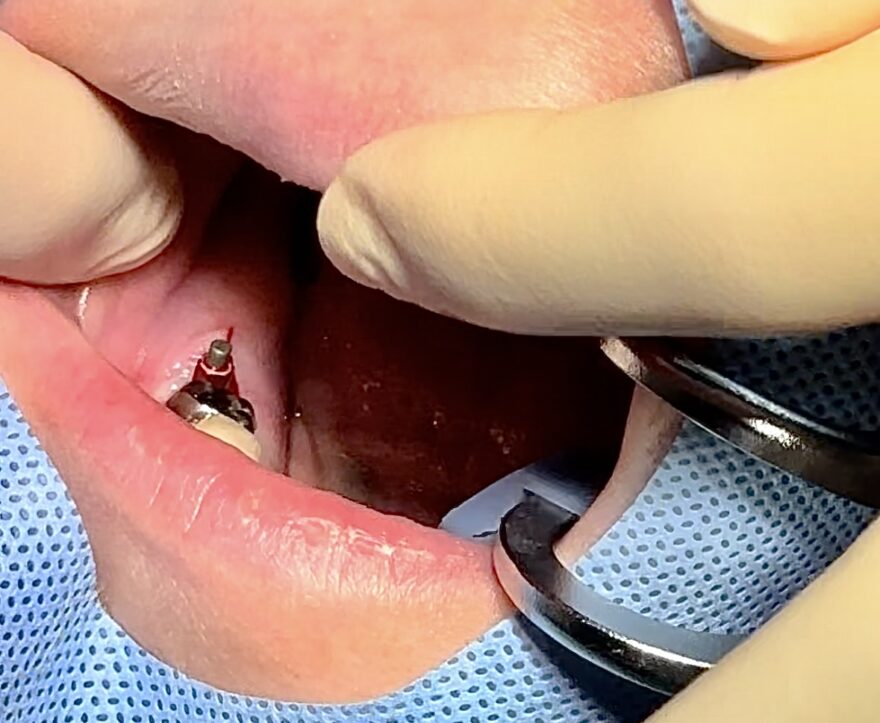

大きく切らず最小限の穴をあけていきます

抜歯も同時にする場合は、抜歯した穴を使ってインプラントを埋入します。

すでに抜歯が済んでいる場合は、少しだけ歯茎を切って骨に穴をあけていきます。

術中の記録は院長の指示のもと、衛生士がしっかりと取っています。

お写真も残しているので安心して下さいね。